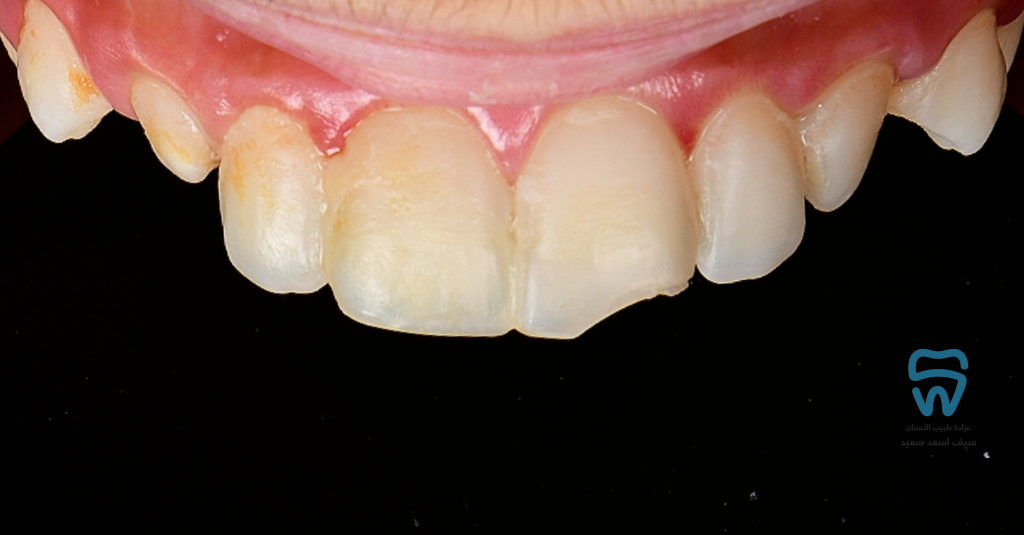

patient came with 2 fractured upper centrals

Complicated crown fracture

At the restoration's polishing visit the patient came back with another trauma on the left central within two days of the restoration